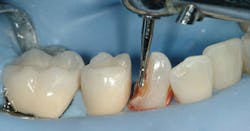

At this point in the treatment, patients should be able to begin a slow and relatively inexpensive way to restore the teeth that had provisional restorations placed in them. Although the carious lesions are large and would be better restored with crowns, consider the following procedure due to the patient's financial limitations. Use build-up techniques on the affected teeth with conventional esthetic restorative materials instead of the relatively unesthetic typical build-up resin-based composites. Most patients have dental benefit plans. Bill these restorations as build-ups (code 2950), not as final restorations. When a patient has adequate financial ability, crowns should be done.

The following images show a patient with limited finances but a strong desire to retain her teeth. The crowns present in the quadrant placed by a previous dentist show that the patient at one time had adequate finances for crowns.

The technique for building up restorations to restore deep carious lesions follows: